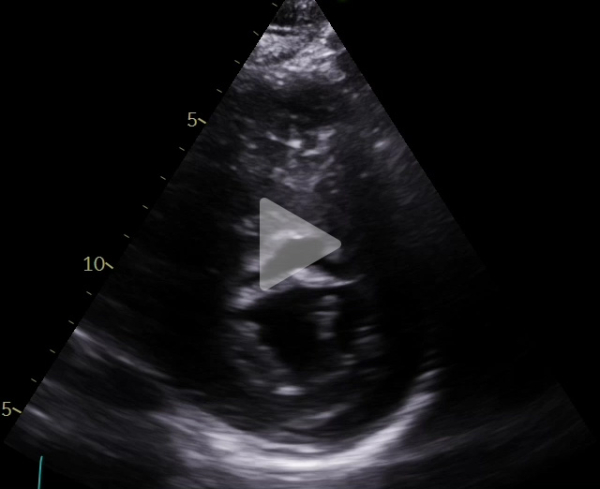

Voici son échocardiographie

Vidéo 4 : échocardiographie 2D en incidence petit axe centrée sur la valve mitrale